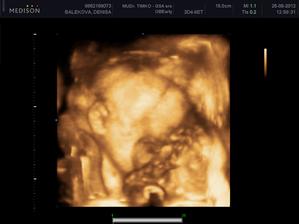

Nas anjelik Alex

Zatial este schovany v brusku ale uz coskoro sa z neho potesime aj nazivo 🙂) Lubime nasho Alexa uz od sameho zaciatku 🙂